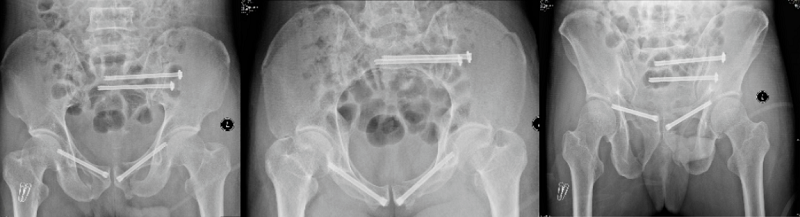

術(shù)前X線片

術(shù)后X線片